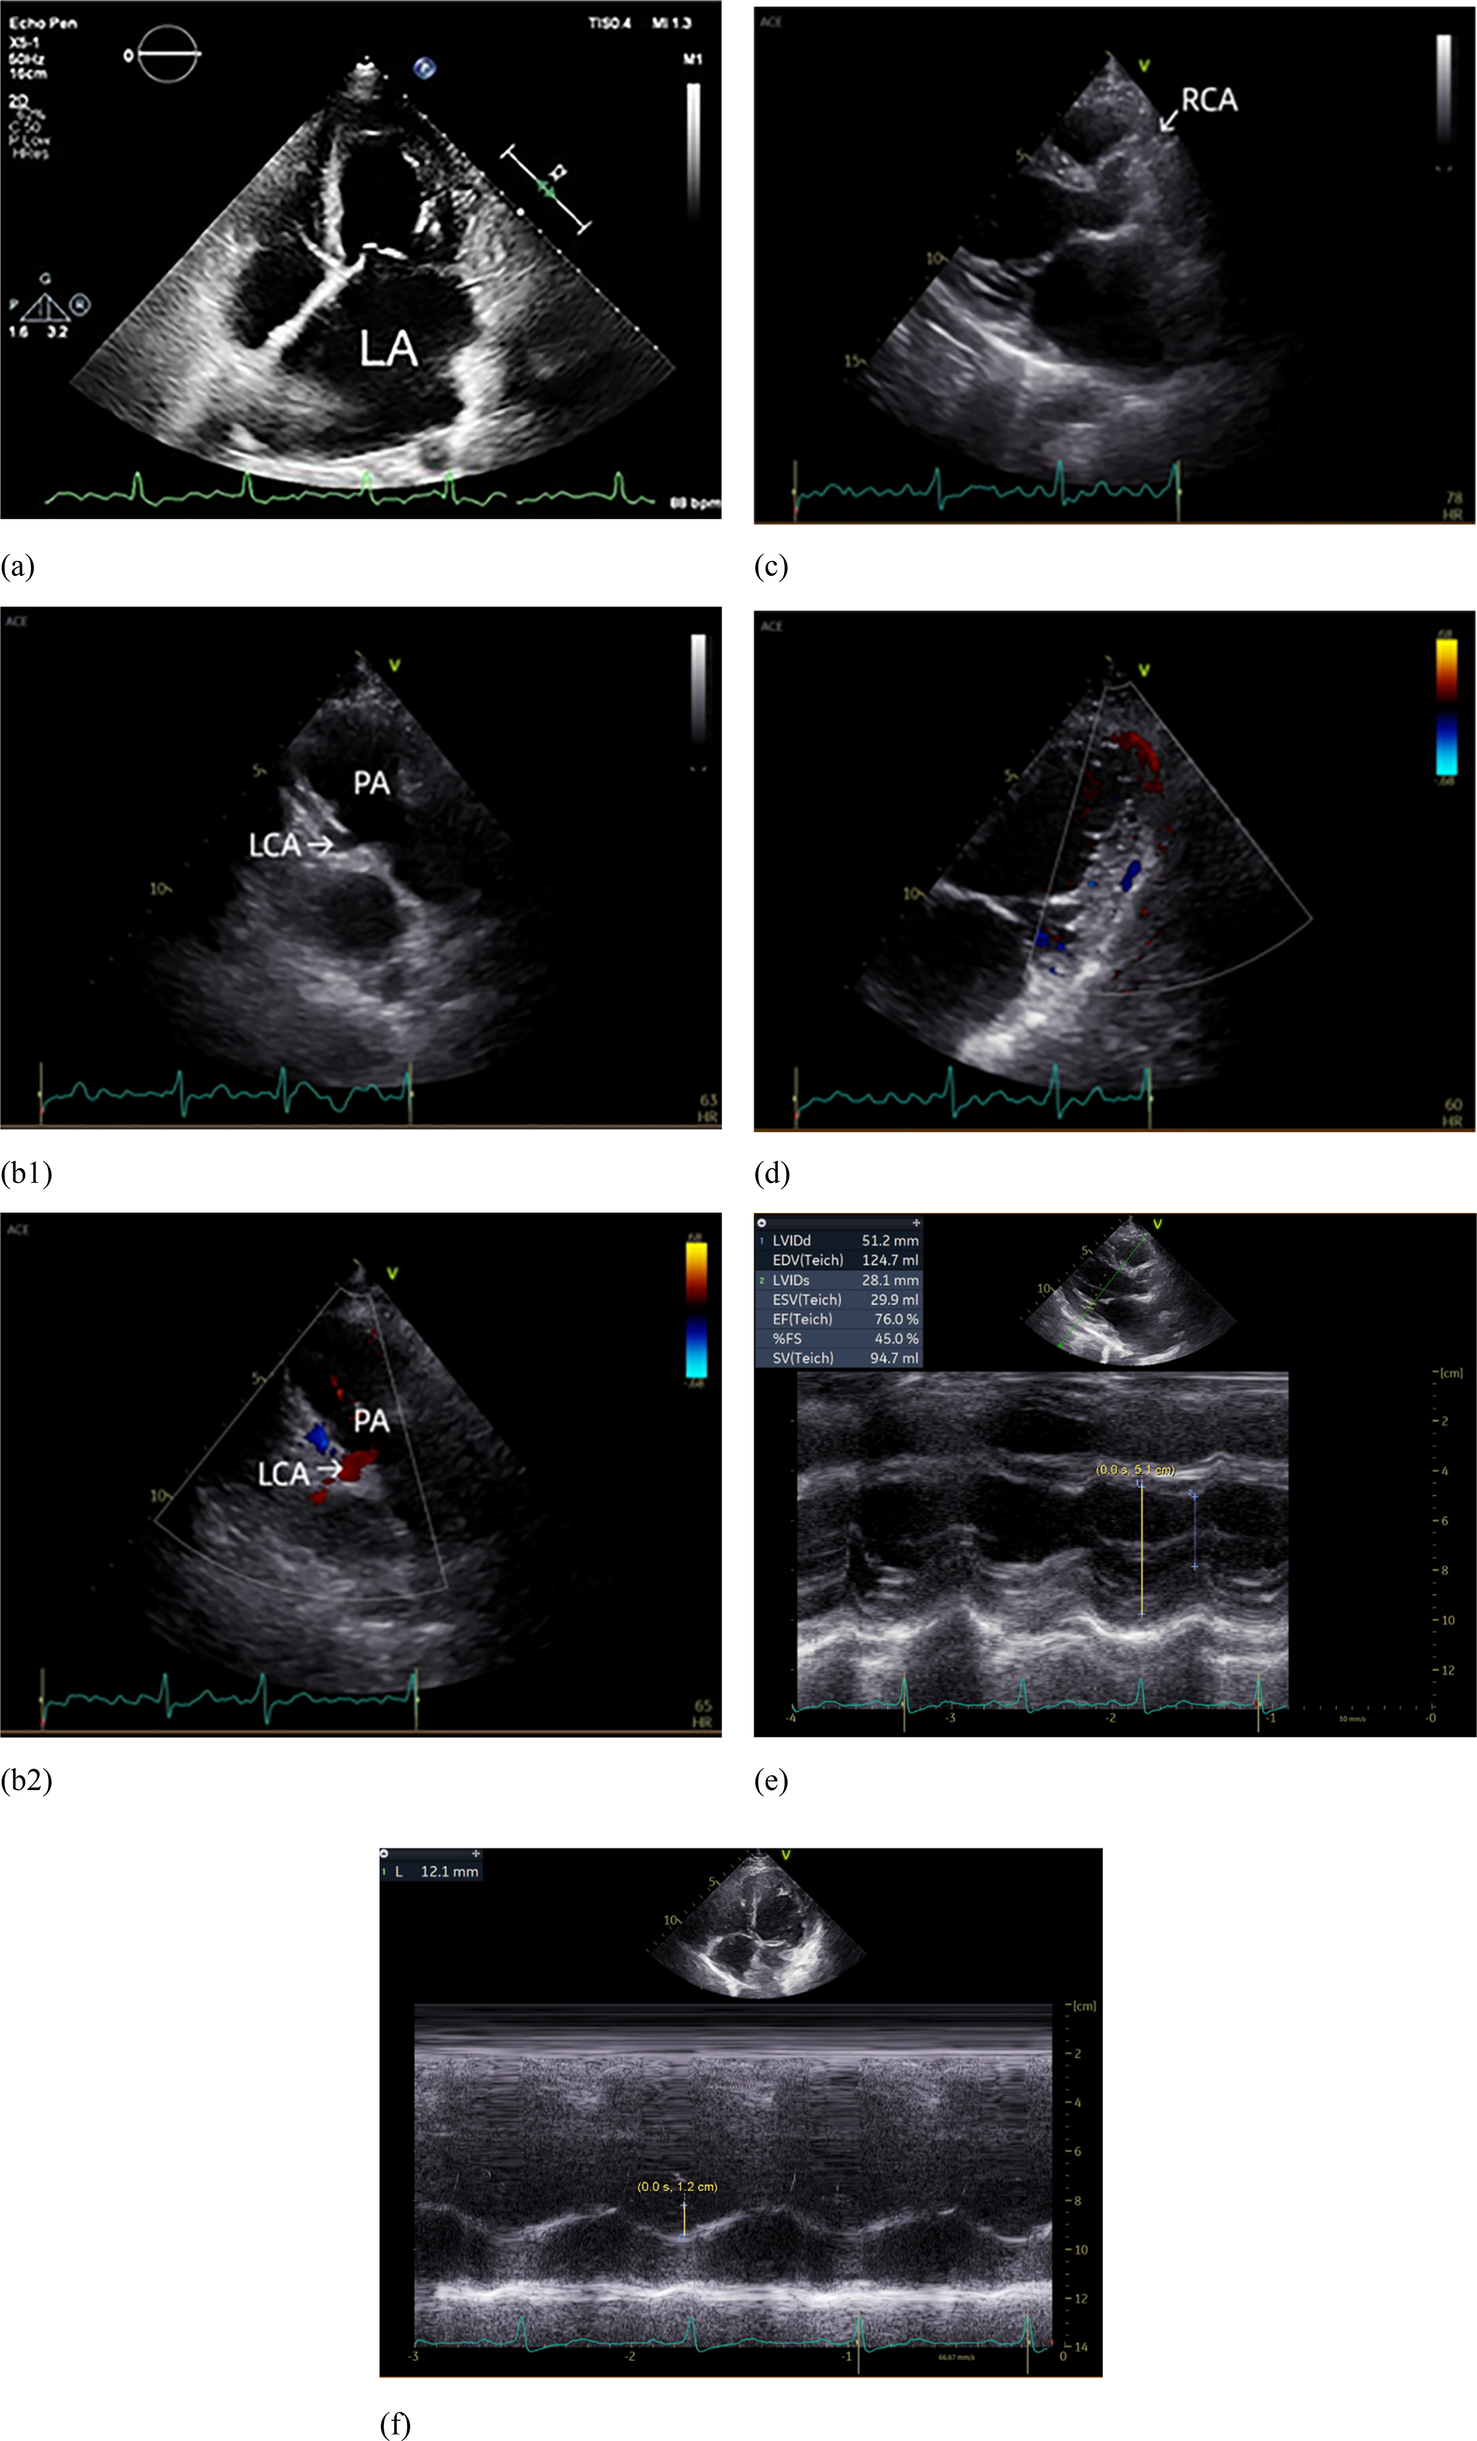

A 28-year-old female was admitted to our hospital due to atrial fibrillation and pulmonary hypertension. She first experienced palpitations at the age of 20, and an ECG confirmed atrial fibrillation. Despite treatment with amiodarone, her condition escalated from paroxysmal to persistent atrial fibrillation. She has not undergone anticoagulation therapy. At the age of 27, her exercise tolerance notably declined, accompanied by chest pain post-activity, and suffered an ischemic stroke. The echocardiography estimated the pulmonary artery systolic pressure (PASP) at 67 mmHg. Although she was treated with oral ambrisentan, her exercise tolerance did not improve, leading her to seek further treatment at our institution. Her medical history was clear of hypertension, diabetes, hyperlipidemia, smoking, drug or food allergies, stimulant use, or any family history of cardiovascular disease. On physical examination, her vital signs were normal, with P2 > A2, irregular heart rhythm, and mild edema in both lower limbs. The patient's thyroid function, hepatic and renal function, high-sensitive troponin I were normal. The N-terminal pro-B-type natriuretic peptide (NT-proBNP) level was elevated at 2,180 pg/ml (normal range: 0–125 pg/ml). Her ECG showed atrial fibrillation with ST-segment depression in leads I, aVL and V4–V6, and poor R-wave progression in leads V1–V3 (Figure 1). Right heart catheterization (RHC) revealed the pulmonary artery systolic pressure, diastolic pressure, and mean pressure were 42 mmHg, 22 mmHg, and 30 mmHg, respectively. The pulmonary capillary wedge pressure (PCWP) was 23 mmHg, and the pulmonary vascular resistance (PVR) was measured at 1.26 Wood Units, suggesting the pulmonary hypertension was related to left heart disease (4). Her transthoracic echocardiography showed a left ventricular ejection fraction of 65%, with an enlarged left atrium with dimensions measuring 48 mm antero-posteriorly, 61 mm superior-inferiorly, and 50 mm transversely, and suspected origin of the LCA from the pulmonary artery. Additionally, the right coronary artery is dilated, and there is visible extensive blood flow communication between the left and right coronary arteries within the myocardium. Echocardiographic evaluation also revealed mild left ventricular enlargement, with left ventricular end-diastolic dimension 51.2 mm and left ventricular end-diastolic volume indexed 74.31 ml/m². Although no regional wall motion abnormalities were observed, the impaired diastolic function (E/e′ ratio 12) indicates chronic ischemia of the left ventricle. There are also signs of right heart dysfunction to chronic pulmonary hypertension with reduced tricuspid annular plane systolic excursion (TAPSE) 12 mm (Figure 2). Further coronary computed tomography angiography (CTA) and coronary angiography showed the left main coronary artery (LMCA) originating from the pulmonary artery, with multiple connections between the distal left and right coronary arteries, and a right coronary to left ventricle fistula (Figure 3 and Supplementary Video S1). Based on these observations, we thought that her clinical manifestations were due to anomalous coronary origin, specifically the abnormal origin of the left coronary artery from the pulmonary artery. The left atrium, mainly supplied by the left circumflex branch (LCX), suffered from prolonged ischemia, leading to structural and electrophysiological remodeling and subsequently to atrial fibrillation and heart failure with preserved ejection fraction (HFpEF), resulting in left heart failure-related pulmonary hypertension, and stroke. She underwent surgery intervention under general anesthesia with hypothermic cardiopulmonary bypass, including the LMCA repositioning and radiofrequency ablation for atrial fibrillation. Postoperative medications included warfarin and aspirin for thromboembolic prophylaxis, amiodarone for rhythm stabilization, and dapagliflozin for optimization in HFpEF phenotype. She was followed up six months after surgery. She regained sinus rhythm, demonstrated a significant improvement in exercise tolerance, and showed a decrease in NT-proBNP levels to 233 pg/ml. Echocardiography revealed a reduction in left atrial size to dimensions of 48 mm × 61 mm × 50 mm (antero-posterior × superior-inferior × transverse diameters) and a decreased estimated PASP from 60–47 mmHg. The timeline of the diagnosis and treatment of the patient is shown in Figure 4.

Figure 2. Echocardiograph. (a) The left atrium was markedly enlarged; (b1) The left coronary artery (LCA) originates from the pulmonary artery (PA); (b2) Blood flow from LCA to PA; (c) The right coronary artery (RCA) originates from the right coronary sinus and is dilated. (d) Intramyocardial visualization of blood flow signals between the LCA and RCA. (e) Dilatation of the left ventricle. (f) Reduced tricuspid annular plane systolic excursion (TAPSE).

In patients with postnatal ALCAPA, the direction of blood flow is usually left-to-right shunting, which has been repeatedly demonstrated (1, 11). Initially, both the LCA and the RCA have normal antegrade flow, because the pulmonary arterial pressure is equal to the systemic pressure (12). However, shortly after birth, the decrease in pulmonary artery pressure causes a reversal of flow in the LCA, causing the LCA to drain oxygenated blood into the lower pressure pulmonary artery. This creates a preferential flow toward the pulmonary circulation rather than the myocardial circulation, which manifests as a left-to-right shunt known as the steal phenomenon (2, 3). This was also verified by the finding of the blood flow from LCA to the pulmonary artery on echocardiography examination (Figure 2b2).